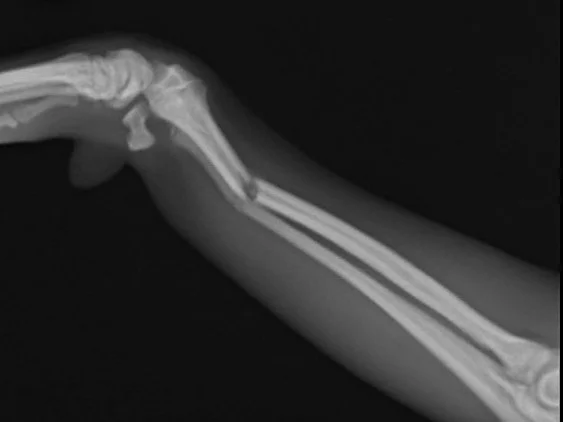

Cats and dogs have bones similar to that of ours (humans), and these bones can get broken in incidents such as falls, fights, car impacts and sports. You may be able to spot an open fracture if the bone penetrates the skin from the inside-out. However, closed fractures (with no open wound) may not be so easily discovered.

When we receive your furkid for assessment, it will likely require an X-ray for close examination of the bones, including sedatives or pain medication. DO NOT FEED them due to potential sedation or anesthesia. We will also likely propose complete bloodwork radiographs and/or ultrasounds to check for vital organ injuries.